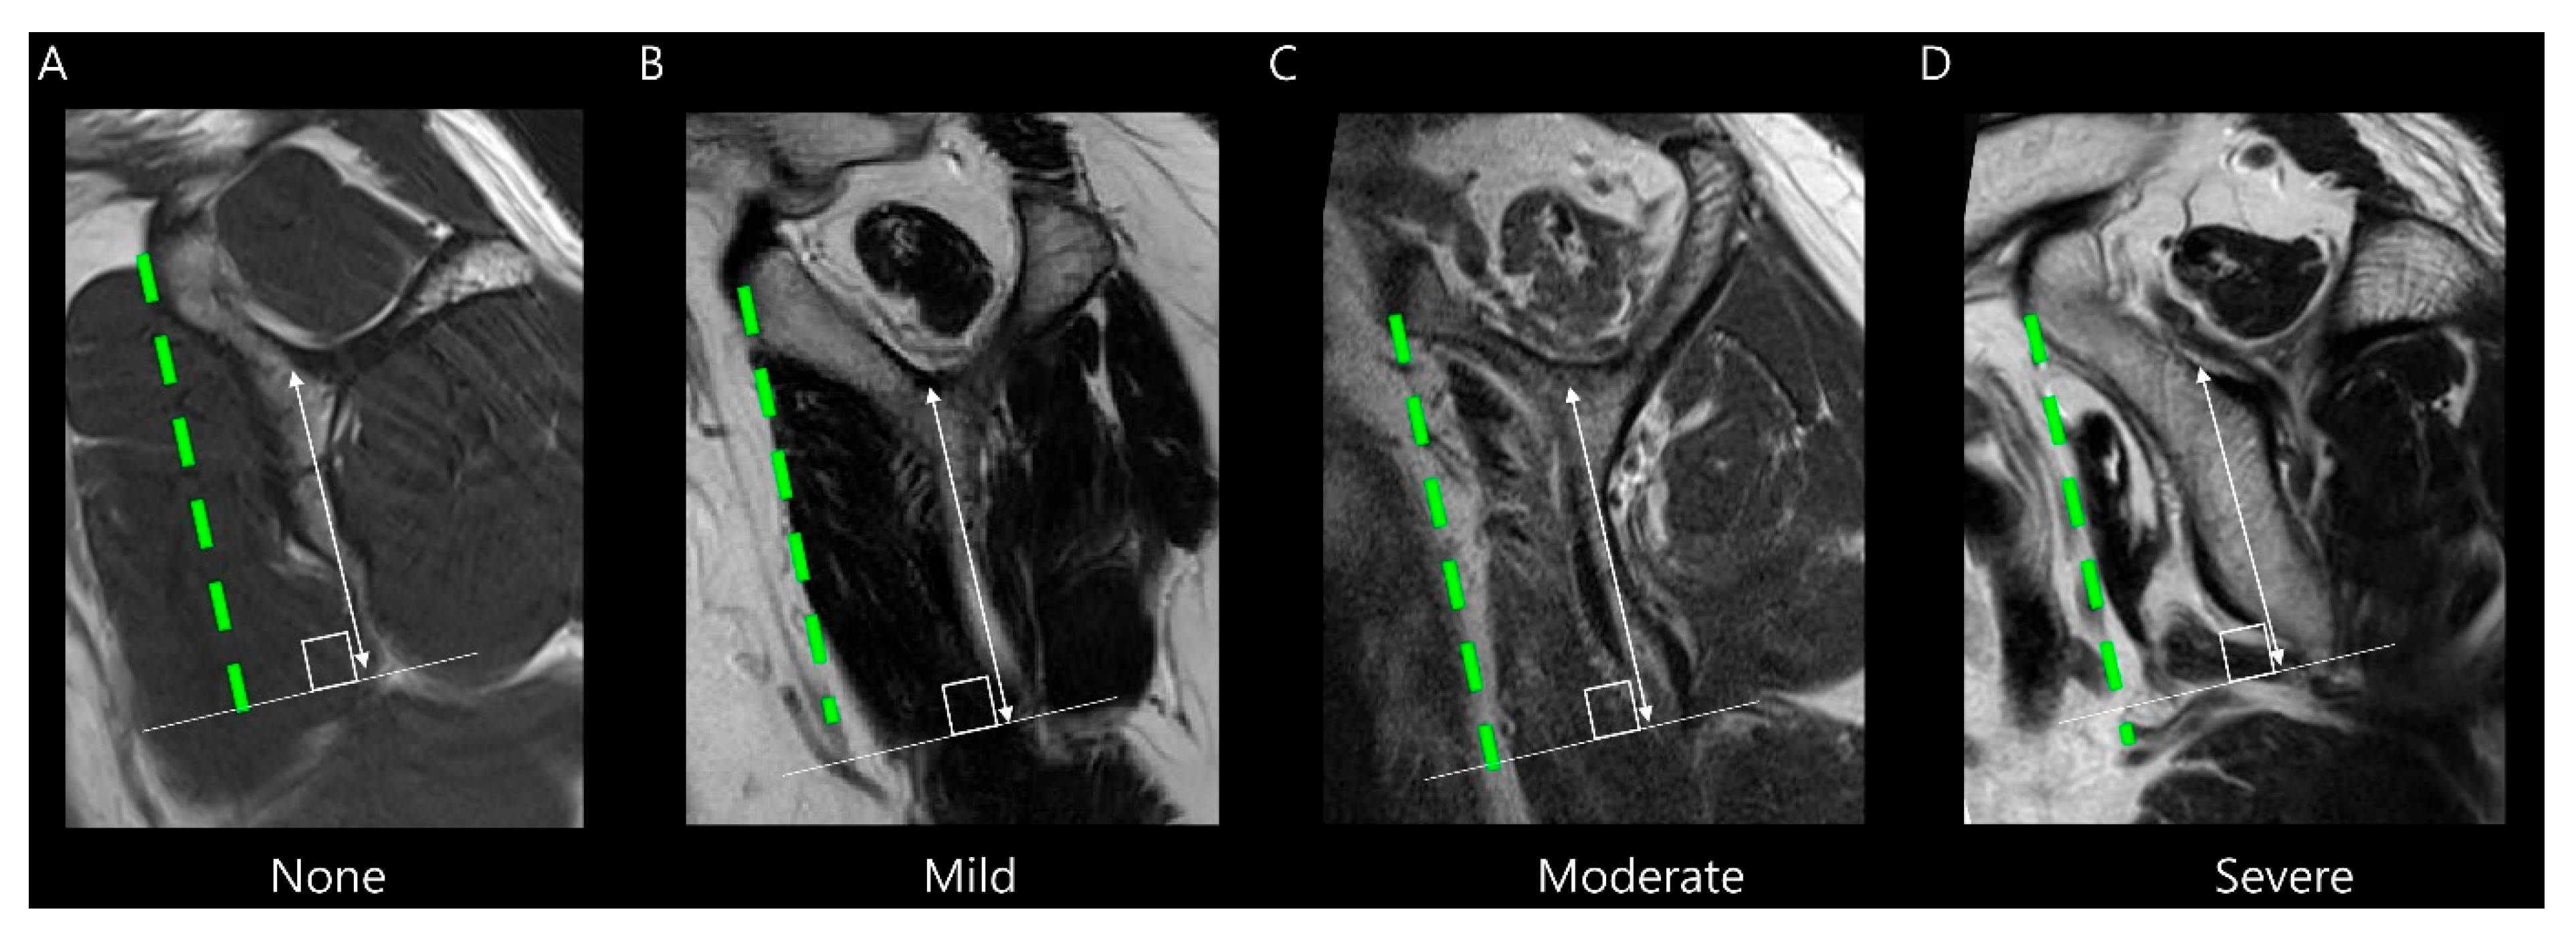

2.3. MRI Analysis

3.2. MRI Findings

| Subscapularis muscle atrophy | <0.001 | κ = 1.000 (p < 0.001) | ||

| None to mild degrees (%) | 110 (99.1) | 21 (65.6) | ||

| Moderate to severe degrees (%) | 1 (0.9) | 11 (34.4) | ||